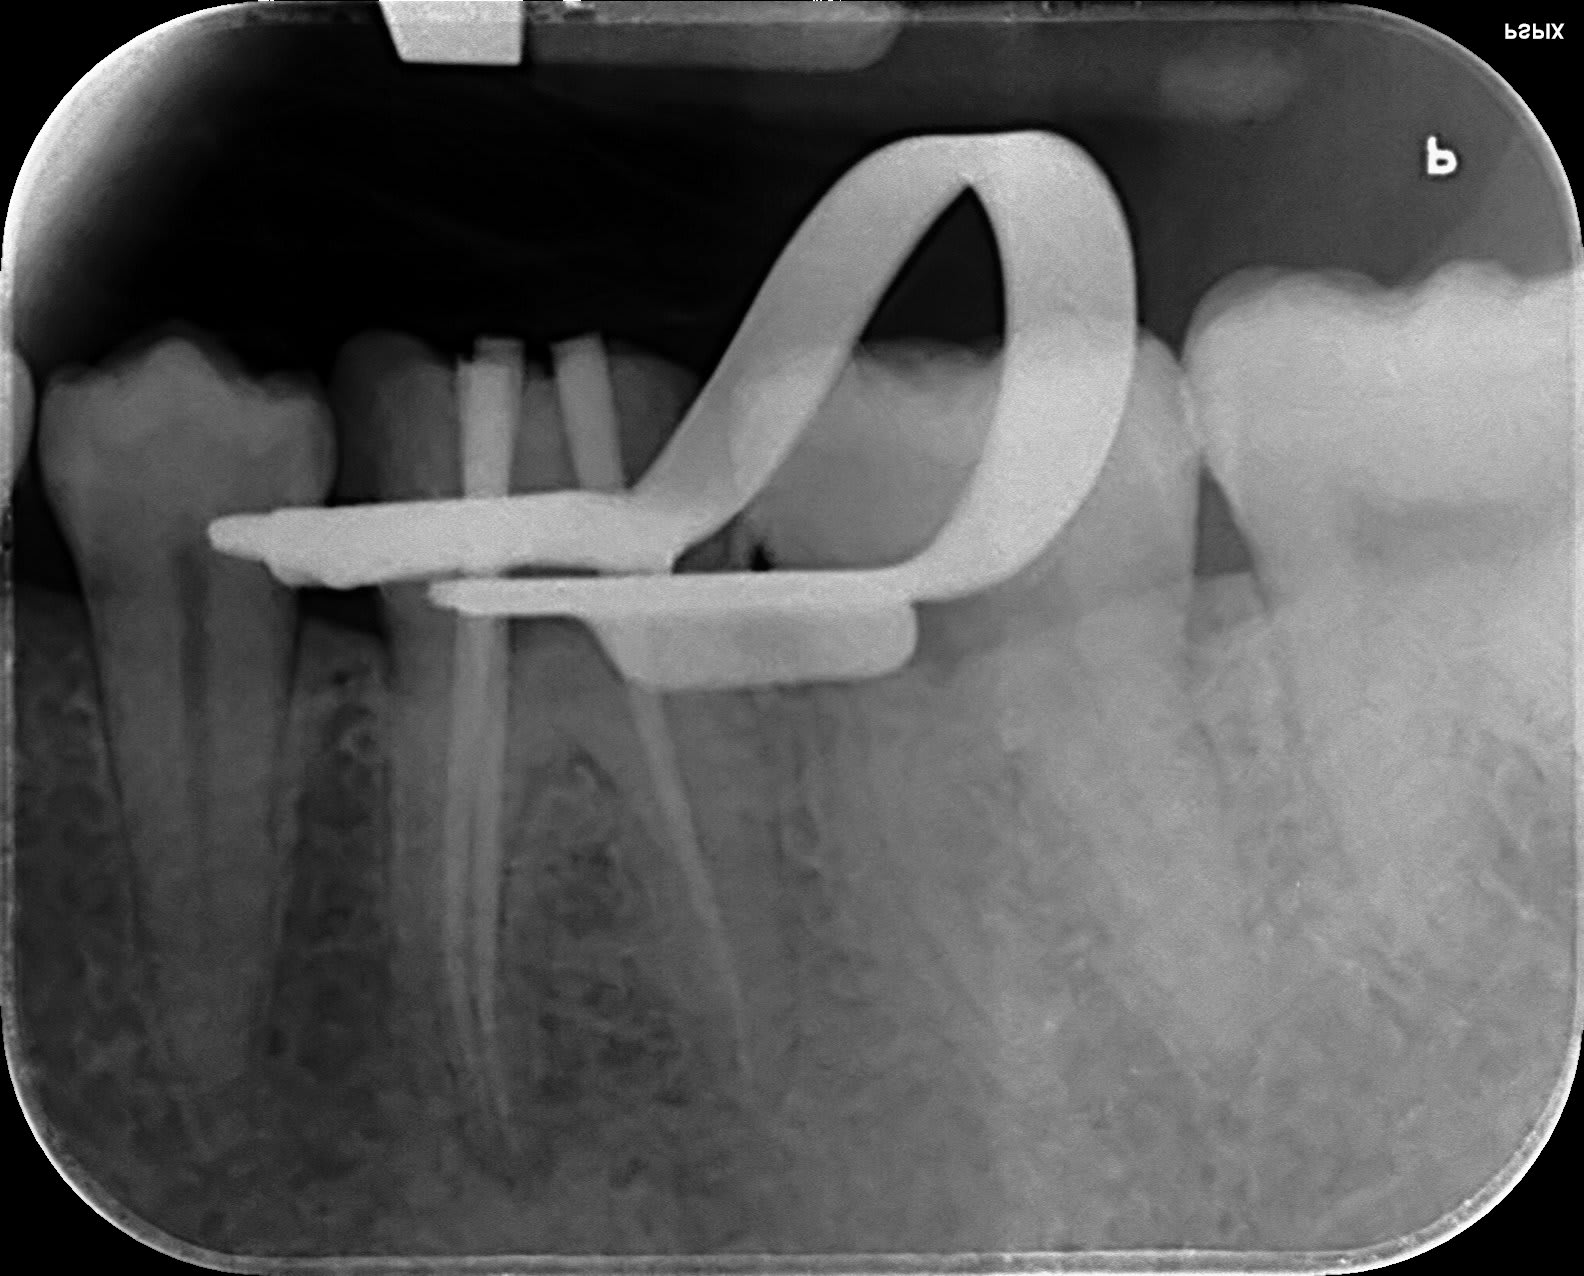

Perso j'aime bien savoir où sont les cônes.

La lime en place je ne la fais plus depuis.... :-)))) que j'ai un localisateur!

Angulateur sur le crampon, facile...

Endo cone en miklw8 - Eugenol

Capture d  cran 2015 03 12 12.28 - Eugenol

chicot29

17/05/2019 à 17h22

Il n'est pas fini votre tt endo cher confrère. Ahhhhhhhh et merde ! D'ailleurs ou est le crampon de digue ? Ca commence à faire beaucoup. -)))